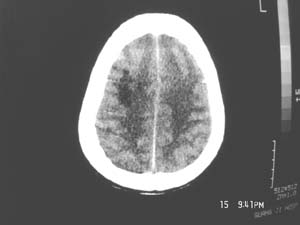

女,60岁,反复头痛3天,呕吐3小时伴昏迷10分钟入院检查。

右额叶占位,有占位效应,中线偏移,病灶位于镰旁,呈囊实性并有钙化,

考虑:1.脑膜瘤。2.胶质瘤。

理由:1.病灶位于前颅凹及镰旁,有明显占位效应---支持脑膜瘤。

2.病灶呈囊实质性并有条状钙化,符合胶质瘤改变;

另外也不排除包虫病的可能。

右额叶占位,有占位效应,中线偏移,病灶位于镰旁,呈囊实性并有钙化 kaolv  少枝胶质瘤。胶质瘤。

病变范围较大,累及左额叶,内见钙化。及高密度灶。考虑;胶母伴卒中可能大。